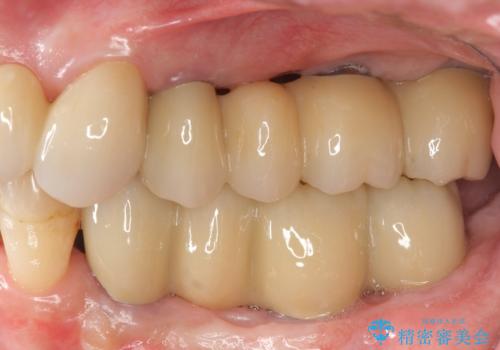

多発した虫歯による咬合崩壊 インプラントを用いた全顎治療

歯の破折・再発した大きな虫歯・根尖病変・歯の欠損、これらの問題を根管治療・歯周外科・インプラント治療・セラミック補綴を行うことで一つづつ解決し安定した咬合状となるよう治療を進めます。

口腔内全体を治療する全顎治療は、期間も長く外科を行う回数も多いためしっかりと通っていただくことが必要不可欠になります。

治療に加えて歯ブラシも上手になることが、治療した歯を長持ちさせるのに必要な要件となります。